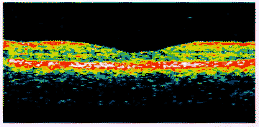

在正常眼黄斑区典型的OCT图像上(图2),不同组织由于反光特性不同在伪彩色图像上呈现为不同颜色:视网膜内界膜和神经纤维层及色素上皮层和部分脉络膜毛细血管所形成的红色反光带界面最为清晰,神经上皮层间呈不均匀的黄绿相间色调,至光感受器层变为暗蓝色,脉络膜反光带呈逐渐稀疏、变淡的蓝色。除以上所述各层外,解剖学对视网膜所分10层中其它各层在OCT图像上难以区分,这是因为在病理切片上因化学性质不同而呈现不同颜色的组织在反光性质上却不一定存在明显区别。

图2 正常黄斑的OCT图像

Fig.2 OCT image of normal macula